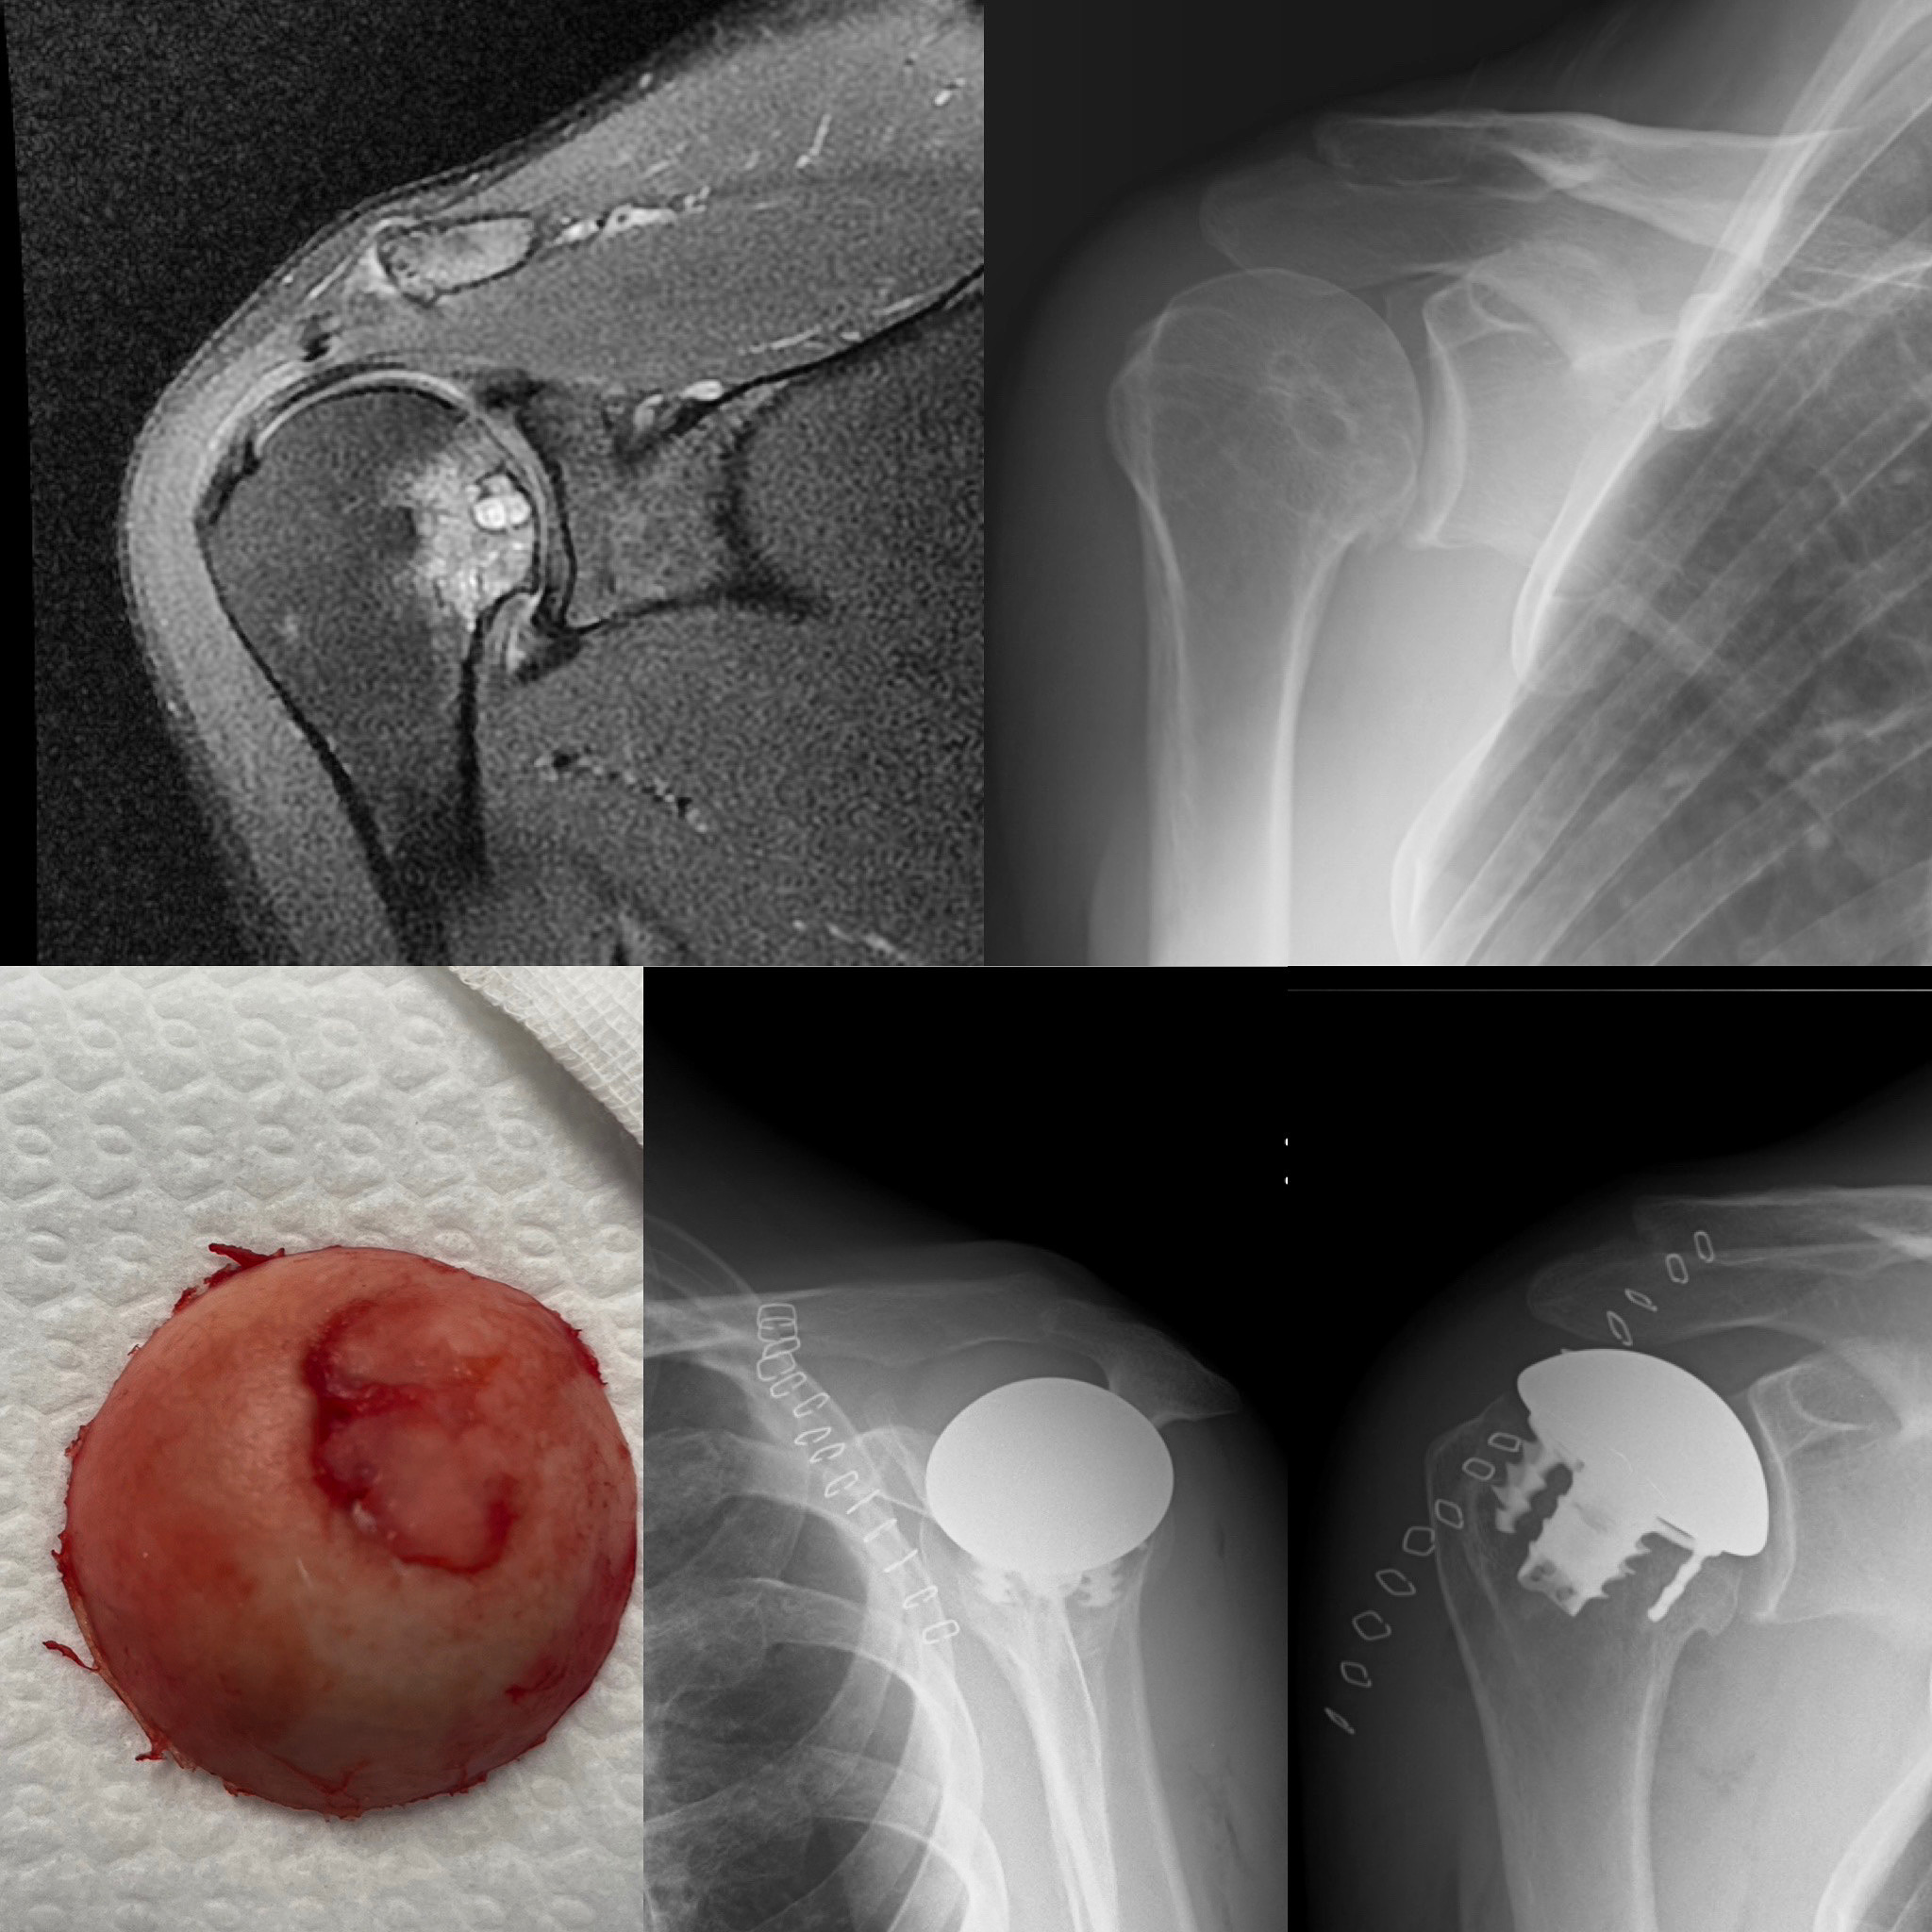

La persistència del dolor i la limitació de la mobilitat progressiva malgrat la fisioteràpia recomanen la realització d'una RM de l'espatlla que permet precisar el diagnòstic, la RM és concloent en la presència d'una necrosi avascular (NAV) del cap de l'húmer amb afectació de superfície articular.

Davant d'aquesta situació, l'opció per millorar el dolor i la mobilitat és la implantació d'un pròtesi de cobriment de la superfície articular.

Aquesta opció és l'aconsellable en un pacient jove i amb aquest diagnòstic en ser la que implica menys pèrdua d'os.

Després del procés postoperatori, la pacient va manifestar una millora progressiva del dolor i va recuperar la mobilitat de l'espatlla.